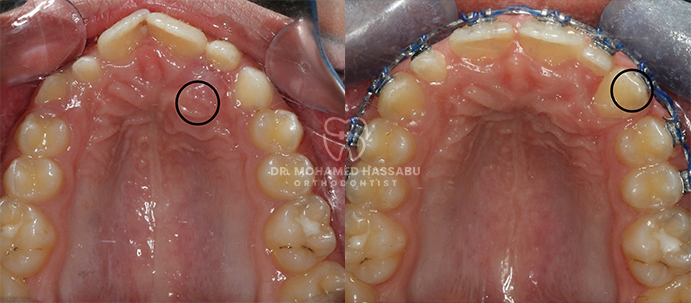

التقويم المعدني عبارة عن أدوات أسنان خاصة مصنوعة من الفولاذ المقاوم للصدأ تساعد في إصلاح الأسنان التي لا يتم محاذاتها بشكل صحيح. تحتوي هذه التقويمات على أقواس معدنية تلتصق بالأسنان وأسلاك رفيعة تعمل على تحريك الأسنان بلطف إلى الأماكن الصحيحة مع مرور الوقت. من خلال ارتداء هذا التقويم، تصبح الأسنان المزدحمة أو الملتوية مستقيمة تدريجيًا، مما يخلق ابتسامة جميلة لك ولطفلك.

تعتبر التقويمات المعدنية ضرورية للعناية بأسنان الأسرة بشكل عام لعدة أسباب. أولاً، إنها تعمل بشكل جيد في إصلاح مشاكل محاذاة الأسنان المختلفة مثل الأسنان المزدحمة أو المتباعدة أو العضة الزائدة أو السفلية. من خلال إصلاح هذه المشكلات في وقت مبكر، يمكن للتقويمات المعدنية أن تمنع حدوث مشاكل الأسنان الأكثر خطورة لاحقًا، مثل صعوبة المضغ أو التحدث. ثانياً، يساعد التقويم المعدني في الحفاظ على الأسنان أكثر نظافة وصحة لأنه يصبح من الأسهل تنظيفها والعناية بها عندما تكون محاذية بشكل صحيح. وهذا يقلل من فرصة الإصابة بالتسوس أو مشاكل اللثة، مما يجعل فمك أو فم طفلك أكثر صحة.

لقد كانت التقويمات المعدنية حلاً موثوقًا ومثبتًا لتقويم الأسنان لأجيال عديدة. إنها فعالة للغاية في تصحيح مشاكل الأسنان المختلفة، بما في ذلك الأسنان المزدحمة، والفجوات، والعضة العلوية، والعضة السفلية. من خلال الضغط بلطف على الأسنان مع مرور الوقت، تقوم التقويمات المعدنية بنقلها تدريجياً إلى مواقعها الصحيحة، مما يخلق ابتسامة متناغمة ومتماسكة.

يقوم التقويم المعدني بتصحيح مشاكل محاذاة الأسنان بشكل فعال، مما يؤدي إلى ابتسامة أكثر صحة وجاذبية.